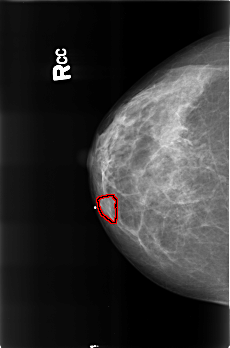

B_3360_1.RIGHT_CC

RIGHT_CC LINES 4512 PIXELS_PER_LINE 2984 BITS_PER_PIXEL 12 RESOLUTION 50 OVERLAY

FILE: B_3360_1.RIGHT_CC.OVERLAY

TOTAL_ABNORMALITIES 1

ABNORMALITY 1

LESION_TYPE MASS SHAPE LOBULATED MARGINS CIRCUMSCRIBED

ASSESSMENT 3

SUBTLETY 4

PATHOLOGY BENIGN

TOTAL_OUTLINES 1

BOUNDARY